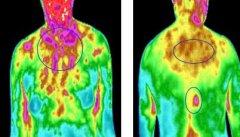

GTT设备的基础原理就是针对人体温度做一个分析,把检查人员的温度分布进行分析,如果身体出现病变的时候温度也会和正常的生理温度不同,这个时候就可以判断出身体的病理状态,

随着科技的发展,医用检查设备是越来越先进,检查方式也是越来便捷。全维度 热成像扫描 ,受检者会面对一台类似于摄像机面前做扫描。它和我们普通摄像机拍到的人像完全不同。

GTT热成像检查是将红外接收器被动接收人体代谢发散红外辐射能,记录转化为数字信号,形成肉眼可见的图像信息,医师从图像了解身体哪里有异常、患病性质或程度。 人体会对外发射

人体是会辐射表征自身温度的红外线,红外辐射强度有一定稳定性,当机体功能出现异常、病变,这个稳定性就会被破坏。 GTT热成像扫描 是一种高新技术,能显示人肉眼看不见的人体